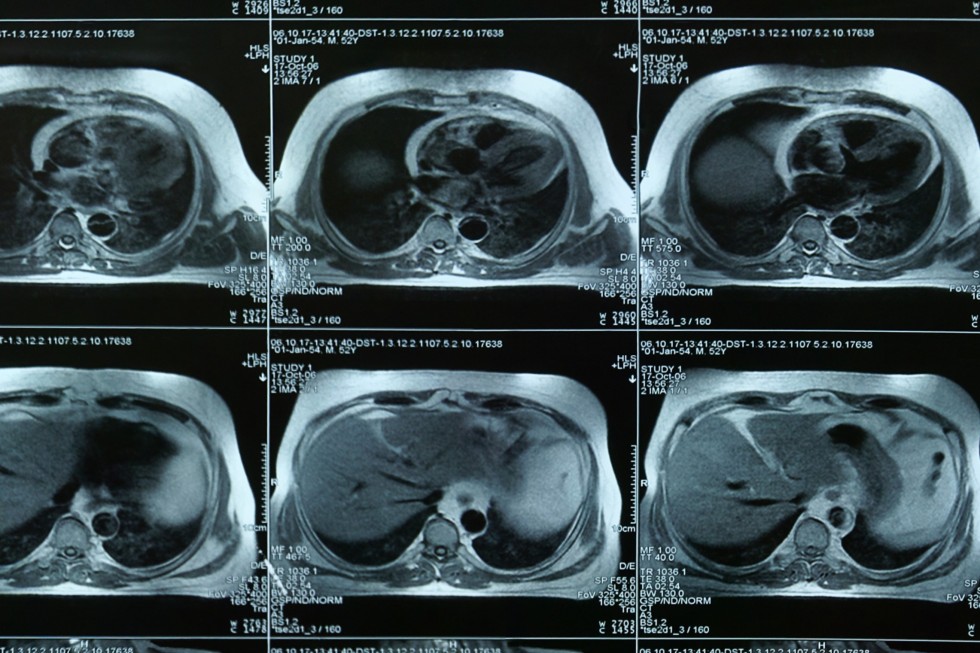

Body imaging specialists have received an additional year of fellowship training beyond radiology residency.  Specializing in interpreting exams and diagnosing diseases related to the chest, abdomen and pelvis, they are experts in reading MRI, CT, Ultrasound, X-ray and Fluoroscopy.